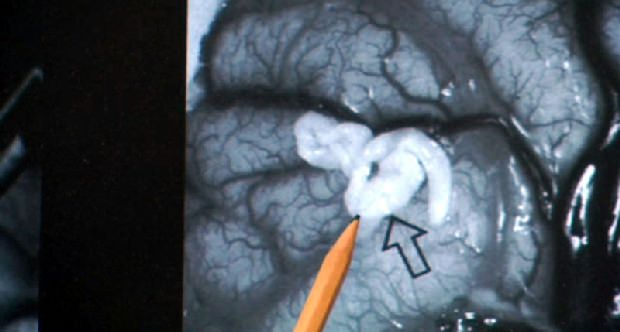

Наиболее обширна группа плоских червей, именно к этому типу относятся трематоды и цестоды — самая частая причина болезней-гельминтозов. Особый интерес специалистов вызывают длинные глисты у человека. Фото таких гельминтов расположено ниже. Оно поможет понять размеры паразитов. А также опасность, которую такие сожители представляют для человека.

Заразиться этим гельминтом можно в странах, традиционно употребляющих в пищу земноводных животных — змей и лягушек, так как именно они являются дополнительными хозяевами гельминта. В среднем длина этого червя достигает 60 сантиметров, но есть сведения о том, что был обнаружен червь около 1,5 метров. Для данного вида гельминта человек — промежуточный хозяин, основным же хозяином будет плотоядное животное семейства кошачьих или собачьих, это могут быть в том числе и домашние кот или собака. Попадая в полость организма человека, личинка червя начинает мигрировать, поражая внутренние органы и системы. В зависимости от места локализации личинки будут зависеть признаки проявления заболевания — спарганоза. Зафиксированы случаи обнаружения личинок Spirometra erinacei в конъюнктиве глаза, под кожей, в нервной ткани. Особо опасен пролиферативный спарганоз. Этот вид заболевания может развиваться у человека до 25 лет и привести к смерти. К счастью, заражение этим видом гельминта у человека наблюдается крайне редко. Диагностируется проблема лишь при анализе удаленной кисты, в которой обнаруживаются личинки гельминта. При церебральных формах спарганоза в диагностике используется томография, способная «увидеть» червя в тканях организма.